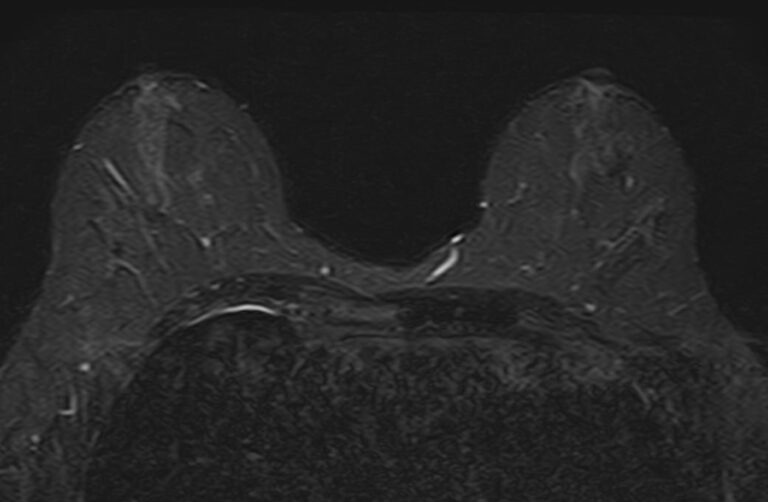

Выполнение МРТ молочных желез без контрастирования возможно для динамического наблюдения состояния имплантатов после пластической операции груди. Во всех остальных случаях во время проведения исследования внутривенно вводится контрастное вещество. Для контрастного усиления применяются препараты на основе солей гадолиния (Магневист, Гадовист и др).

- Для оценки состояния силиконовых имплантов после пластики груди;